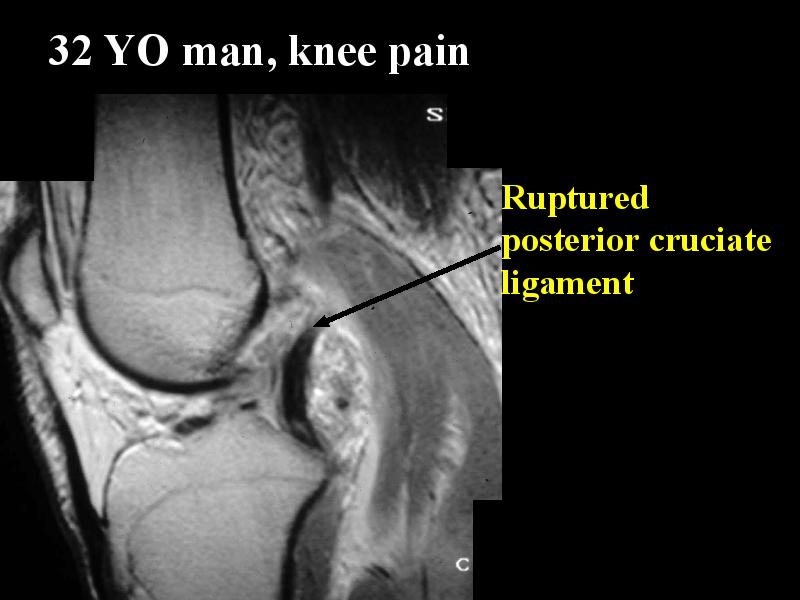

MS 127 MR TEAR ANT POST CRUC